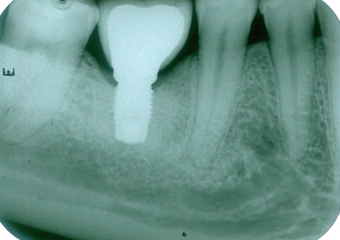

Raio X do implante instalado, com cicatrizador